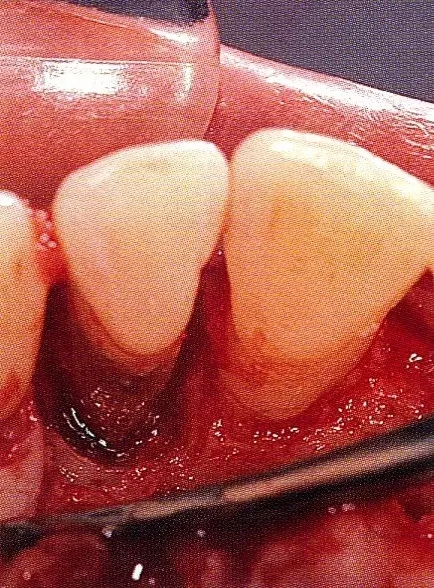

▲圖7-4  術(shù)后1年2個(gè)月再翻開看的情況。與圖7-1的骨缺損狀態(tài)相比可知形成了臨床性骨再生。